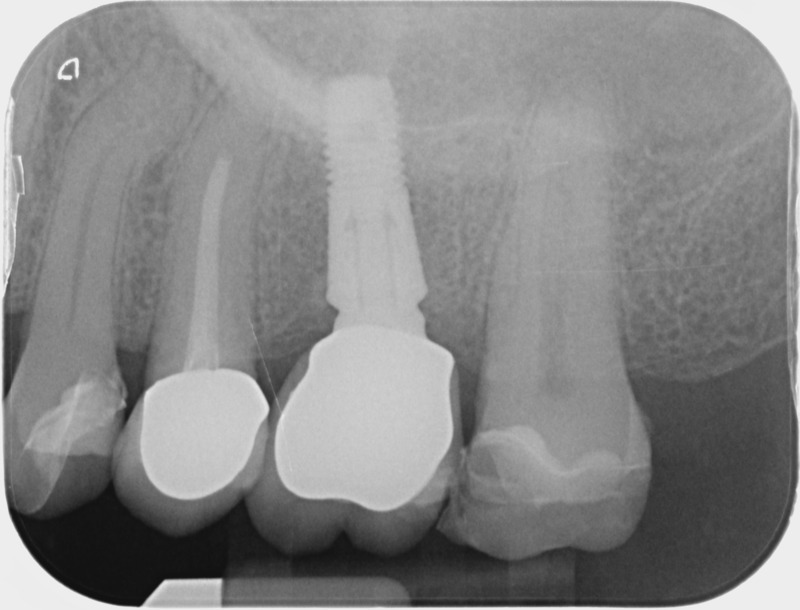

Après

• Reprise de traitement endodontique : La manœuvre consiste à retourner à l’intérieur des racines d’une dent déjà traitée. Il arrive occasionnellement qu’une nouvelle inflammation se déclare suite à une reprise de carie ou une fracture de la dent, ou si le premier traitement endodontique est incomplet. Après s’être assuré que la dent lésée était conservable, il convient de désinfecter de nouveau le réseau canalaire parfois très complexe. La nouvelle obturation des canaux devra être protégée aussi rapidement que possible pour éviter une éventuelle contamination bactérienne.

Avant